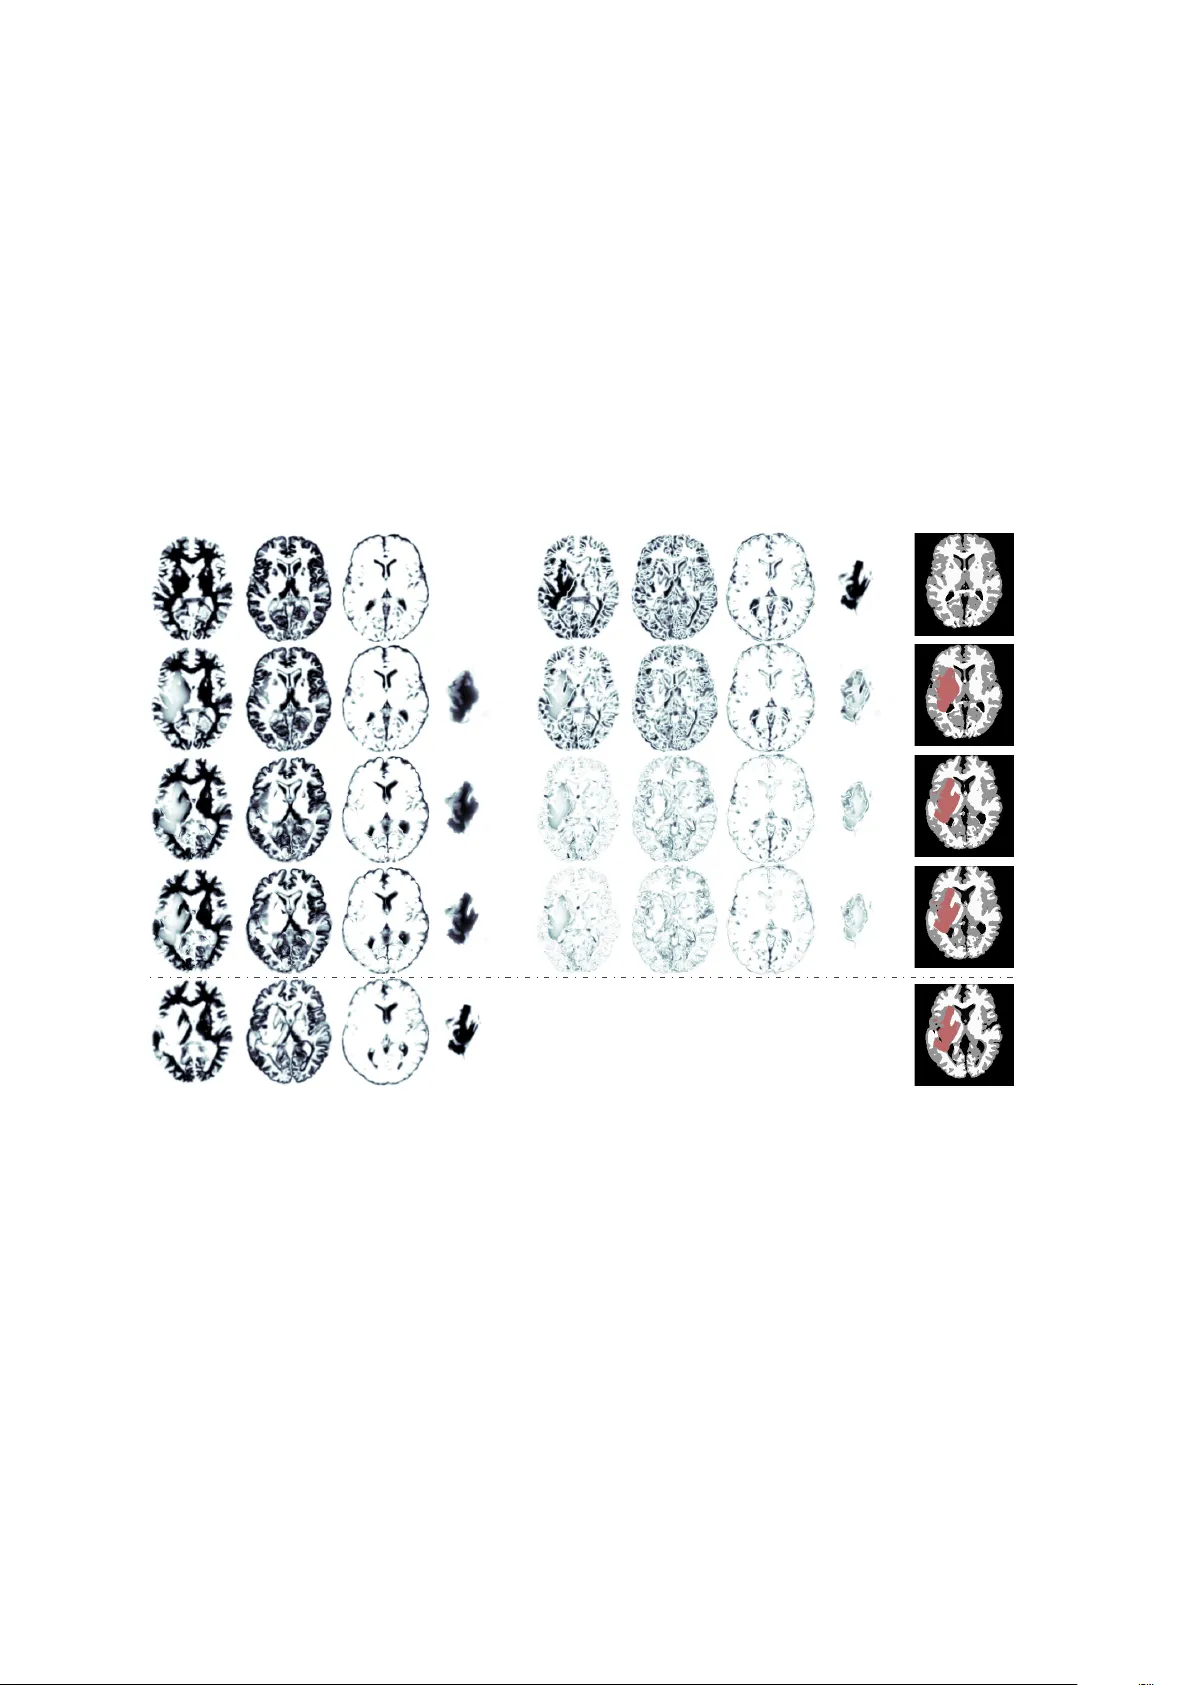

We present the SIBIA (Scalable Integrated Biophysics-based Image Analysis) framework for joint image registration and biophysical inversion and we apply it to analyse MR images of glioblastomas (primary brain tumors). In particular, we consider the f…